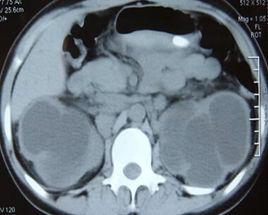

4. 尿崩症:為中樞性,發生率約為32%,此外尚有腎盂積水,輸尿管積水,低張力性膀胱等。